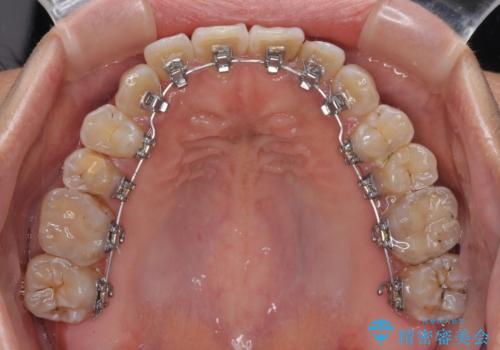

- リンガル

- 3年8ヶ月

- 30回以上

途中転勤や出産があり、通院できない期間が長くありましたが、無事に歯列を整えることができました。